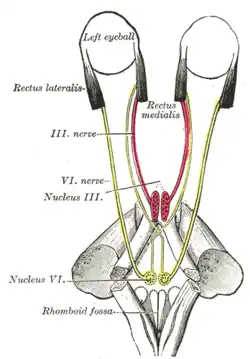

Figure showing the mode of innervation of the Recti medialis and lateralis of the eye. Human caudal brainstem posterior view

Human caudal brainstem posterior view